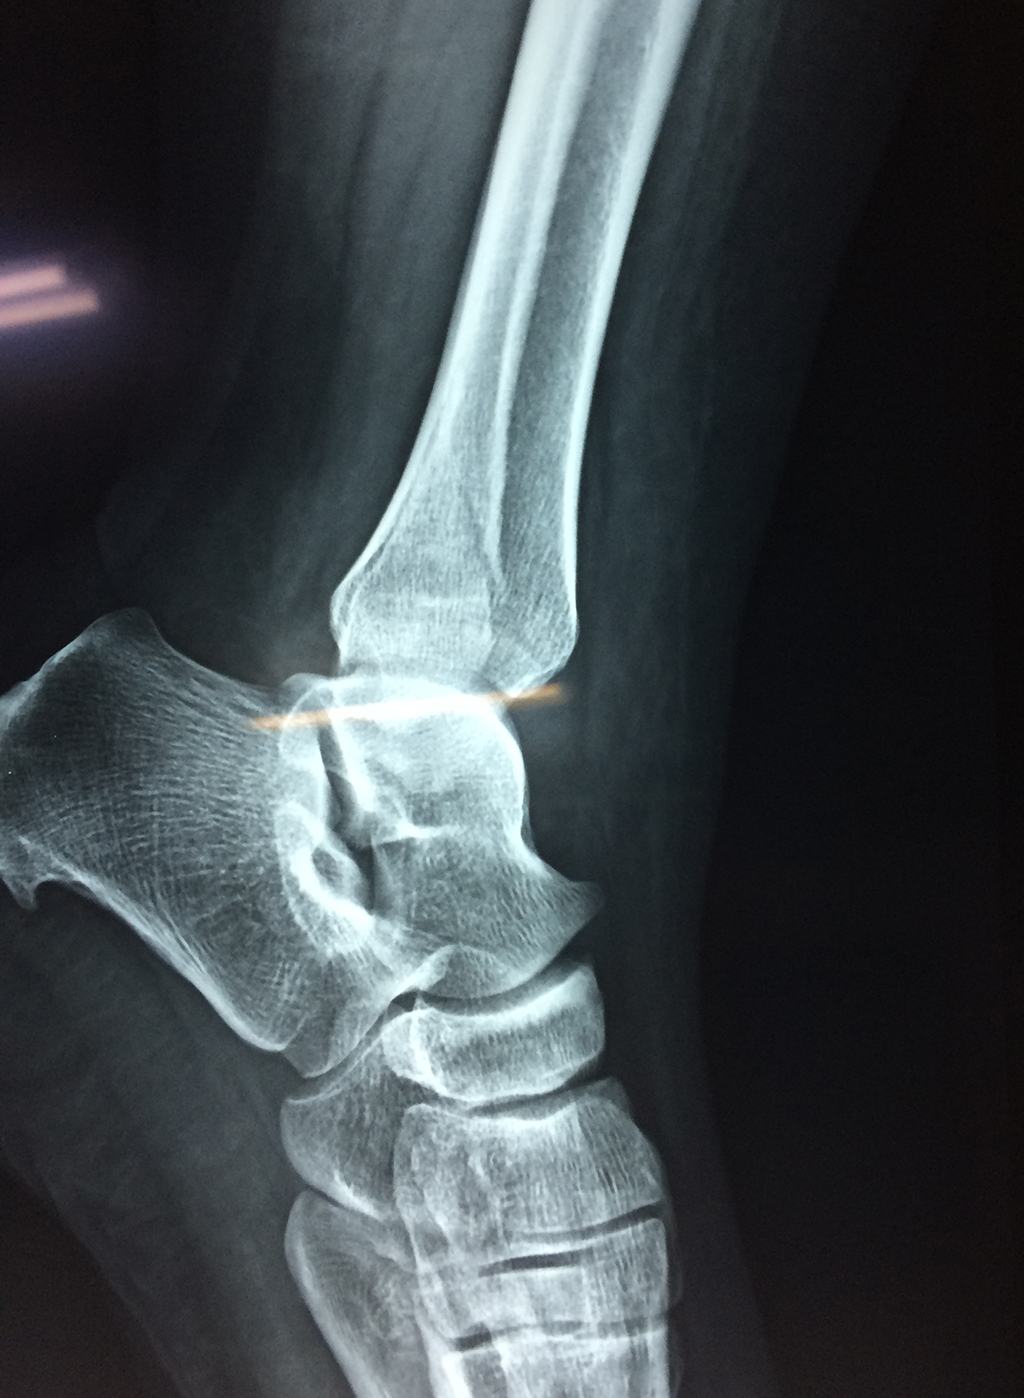

Una fractura de tobillo es la rotura de uno o más de los huesos del tobillo. Estas fracturas pueden ser:

- Parciales (el hueso está sólo parcialmente fisurado, no del todo).

- Completas (el hueso está perforado y está en 2 partes).

- Producirse en uno o ambos lados del tobillo.

- Los extremos de los huesos están desalineados entre sí (desplazados).

- La fractura se extiende hasta la articulación del tobillo (fractura intra-articular).

- Los tendones o ligamentos (tejidos que sujetan los músculos y los huesos entre sí) están rotos.